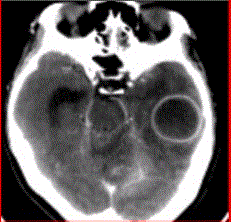

问题 患者女,26岁,头痛、低热10d余,既往有左侧慢性中耳炎病史。CT表现如下图。 有关脑脓肿的DWI表现,正确的是

选项 A.DWI上脓肿腔均呈高信号,ADC呈低信号 B.经过治疗的脓肿腔DWI也可呈等信号或低信号 C.DWI脓肿周围水肿高信号,ADC高信号 D.DWI上脓肿腔低信号,ADC高信号 E.脓肿壁DWI高信号